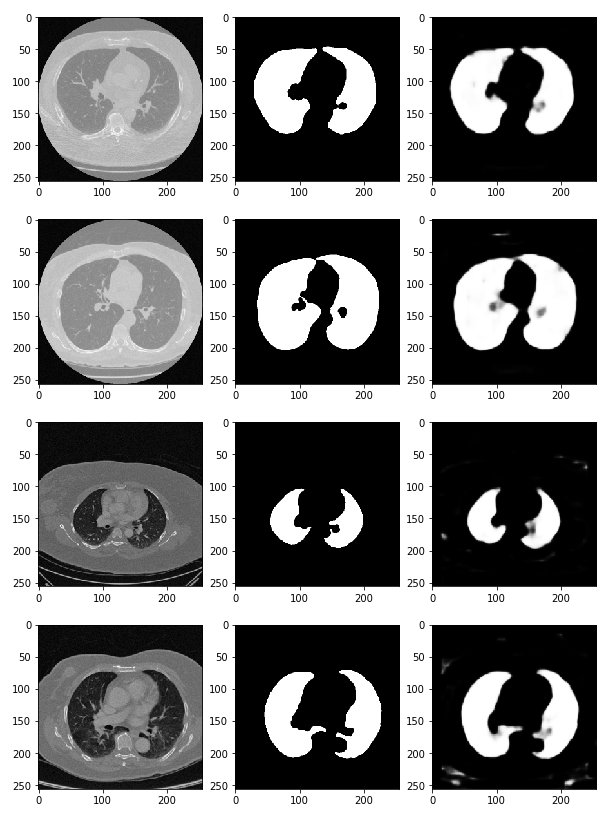

preds = model.predict(x_val) # predict 함수를 통해 (x_val) 검증한다

fig, ax = plt.subplots(len(x_val), 3, figsize=(10, 100))

for i, pred in enumerate(preds):

ax[i, 0].imshow(x_val[i].squeeze(), cmap='gray') # 첫 번째 열에는 CT 데이터(x_val[i])를 삽입

ax[i, 1].imshow(y_val[i].squeeze(), cmap='gray') # 두 번째 열에는 정답 데이터를 넣는다.

ax[i, 2].imshow(pred.squeeze(), cmap='gray') # 세 번째 열에는 우리가 예측한 결과값을 그려본다.

# 이러한 딥러닝을 활용하여 산소의 수치, 적혈구, 백혈구의 농도 등 수치적 데이터를 가지고 예측하는 방법도 존재함.